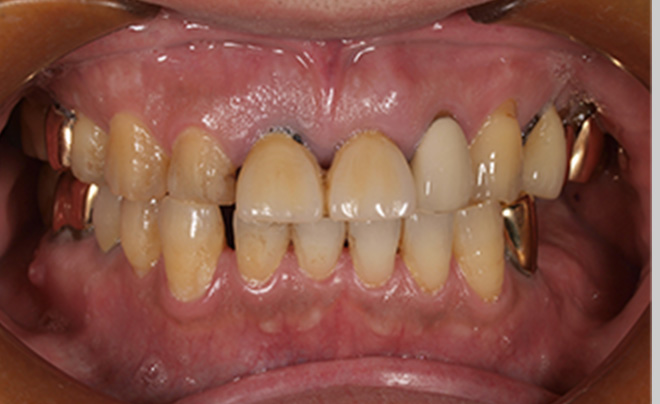

Before

After

| 55歳 男性 | |

|---|---|

| 主訴 | 前歯でしか咬めなく、食事を摂るのに非常に困難で辛い |

| 処置内容 | 上顎6本、下顎3本 |

| 治療費用 | 上顎: 約230万(税込) 下顎: 約120万(税込) |

| 治療期間 | 上顎: 1年(仮歯まで8ヶ月) 下顎: 8ヶ月(仮歯まで5ヶ月) |

| リスク | 上部構造物、仮歯の破折、術後の腫れ(3日)、人工歯根脱落リスクがあります |